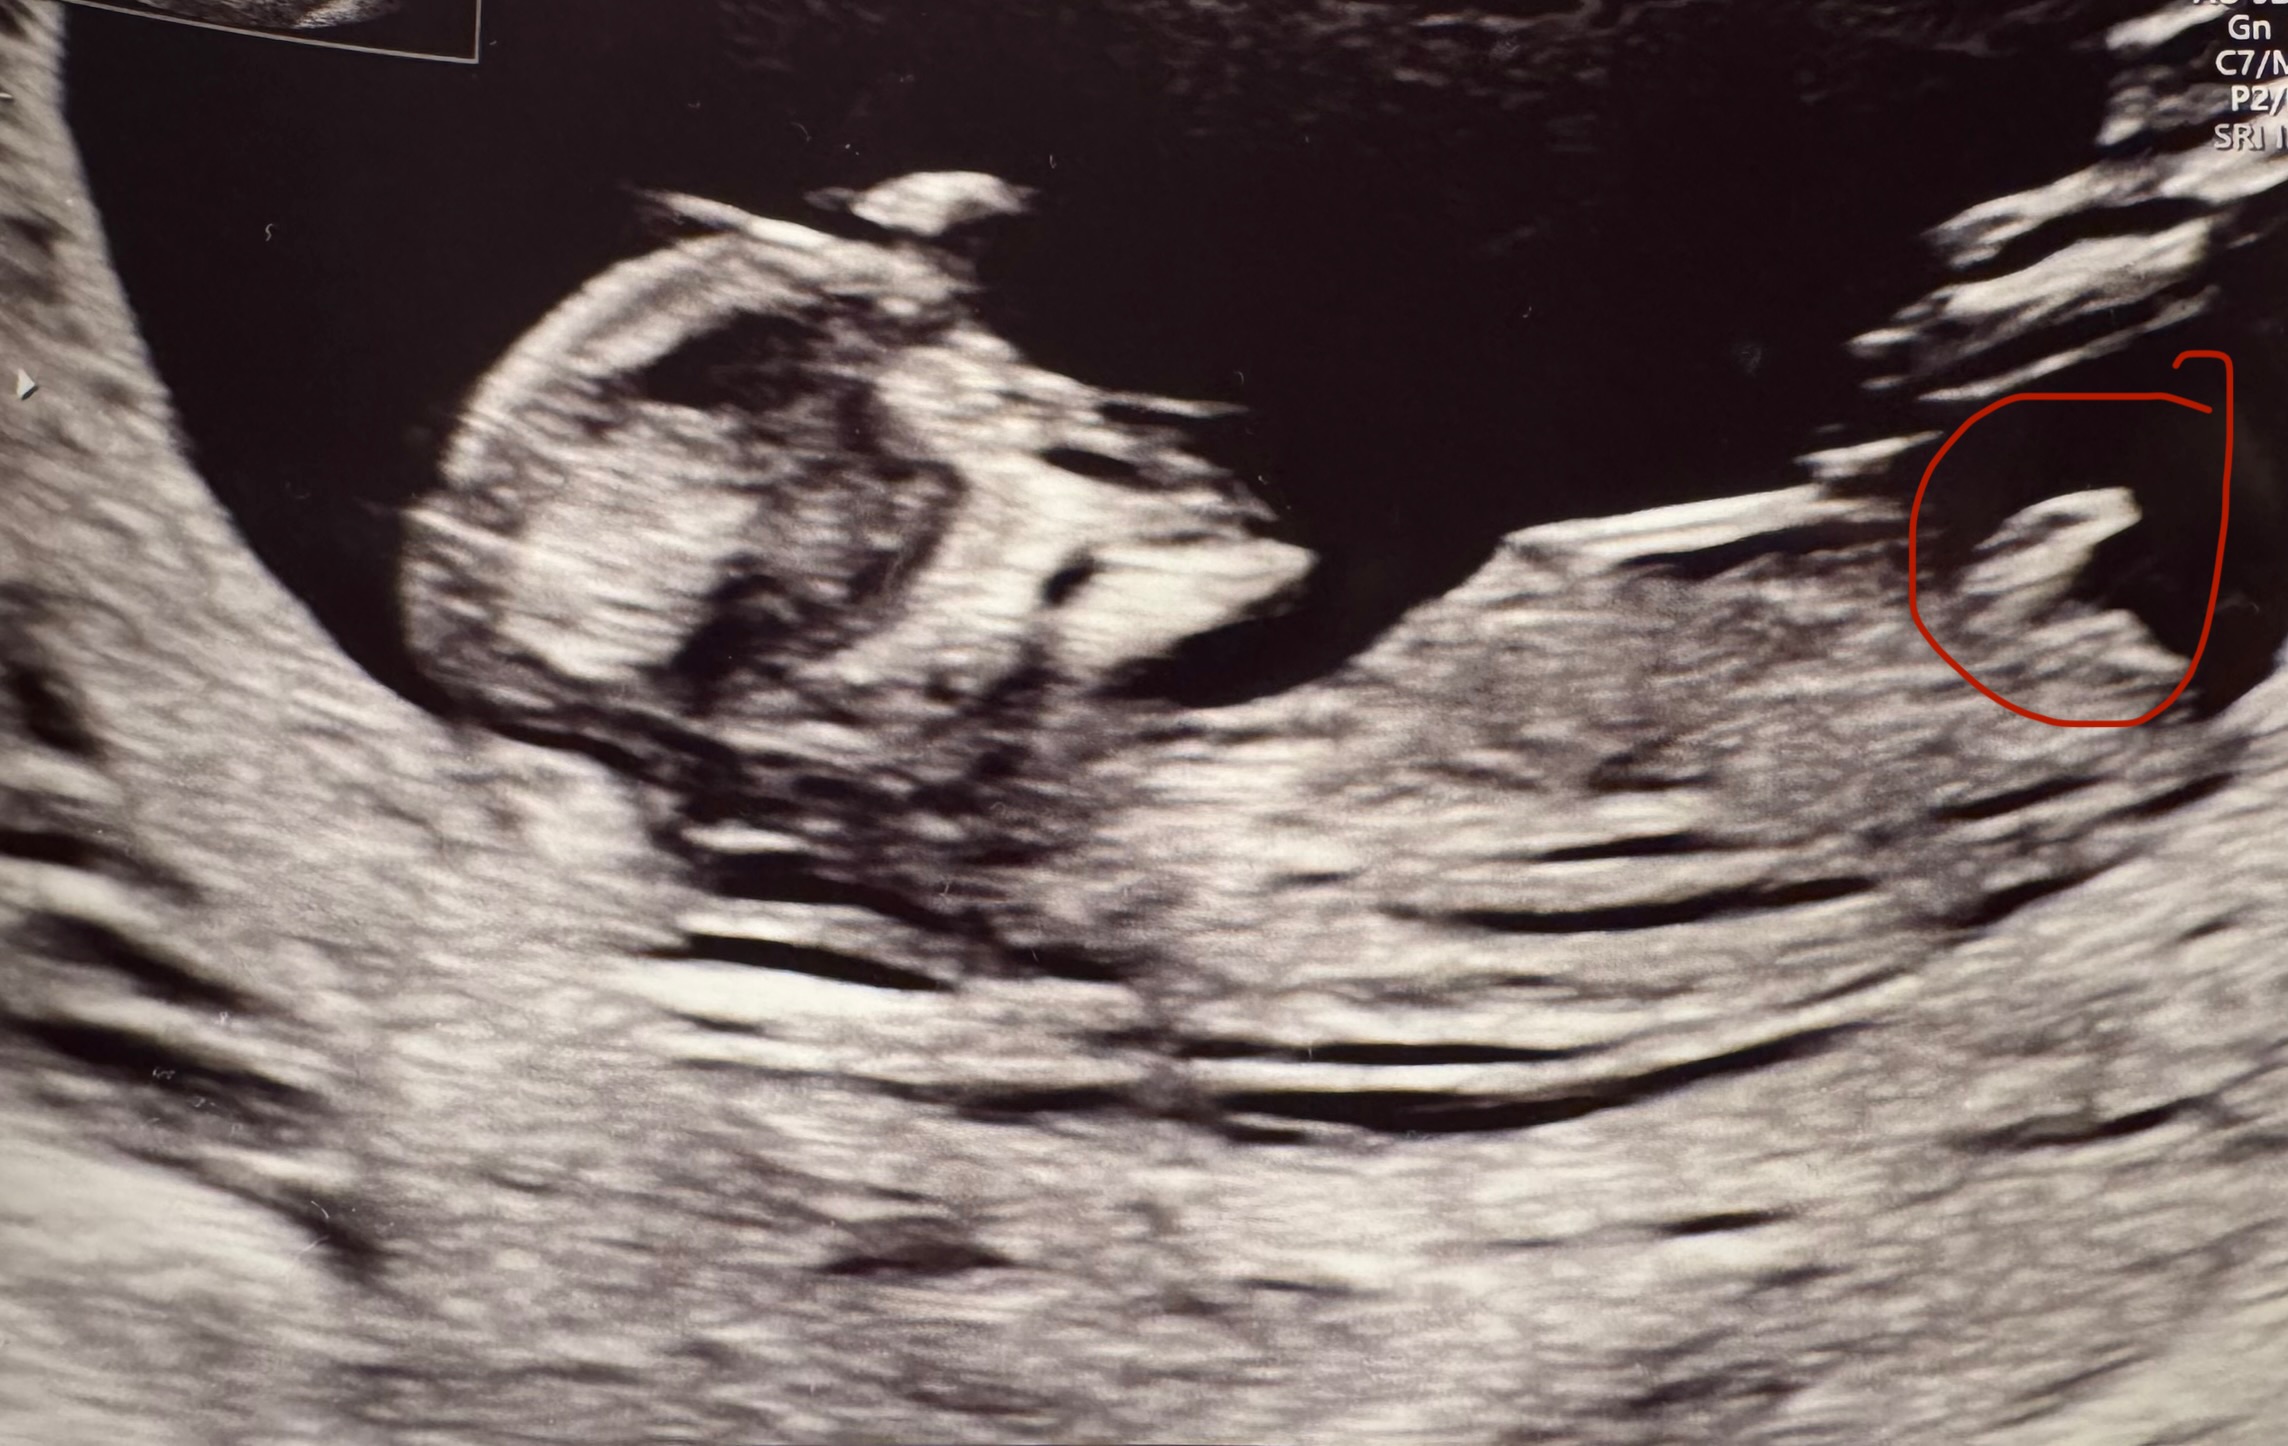

Heippa,

Osaako joku arvioida meidän kuvasta? Kätilö sanoi, että tuo ympyröity olisi napanupra, eikä siitä voi päätellä mitään. Facebookin nub-teoria ryhmässä sanottin, että se olisi nub?!

Rv 12+3.